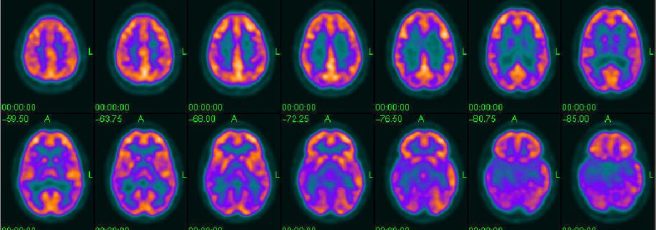

7. New PET imaging ligands

An alpha-synuclein PET ligand: Researchers have a bioRxiv manuscript presenting C05-05 – a bimodal imaging probe for visualizing Parkinson’s-associated α-synuclein inclusions in the CNS of living animals (mice & primates) modeling α-synuclein propagation (Click here to read more about this). The same researchers also published a report on another imaging probe, PM-PBB3, that captures pathological tau deposits in vivo with high contrast; allows an individual-based identification of Alzheimer’s & non-AD tauopathies (Click here to read more about this).